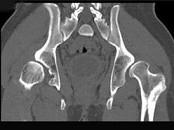

问题 男,23岁,跛行,外展受限,两下肢不等长,结合图像,最可能的诊断是?(?)

选项 A.髋关节中心脱位 B.髋关节后脱位 C.髋关节前脱位 D.先天性髋内翻 E.髋关节结核

答案 B